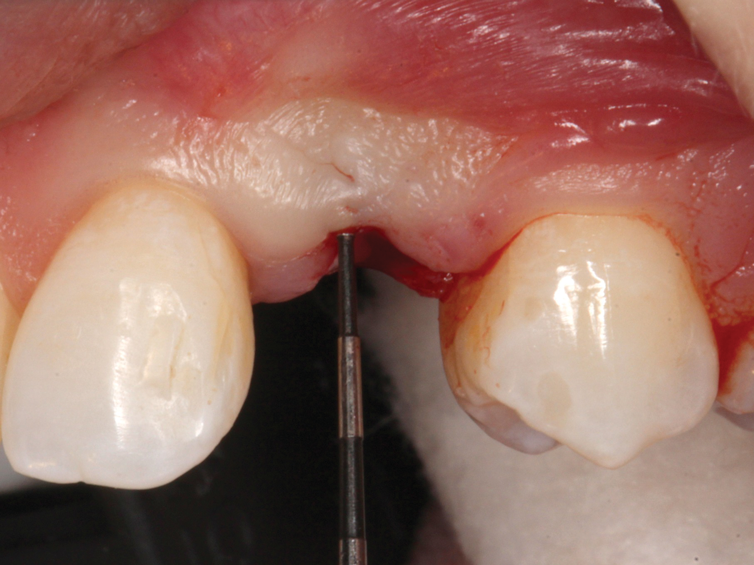

(35.) An implant being inserted into the prepared osteotomy of a patient who presented for the replacement of the maxillary left central incisor.

Figure 35

(36.) The implant’s primary stability was assessed by RFA, and the ISQ value greater than 65 was used to determine that immediate provisionalization was indicated.

Figure 36

(37.) The implant’s primary stability was assessed by RFA, and the ISQ value greater than 65 was used to determine that immediate provisionalization was indicated.

Figure 37